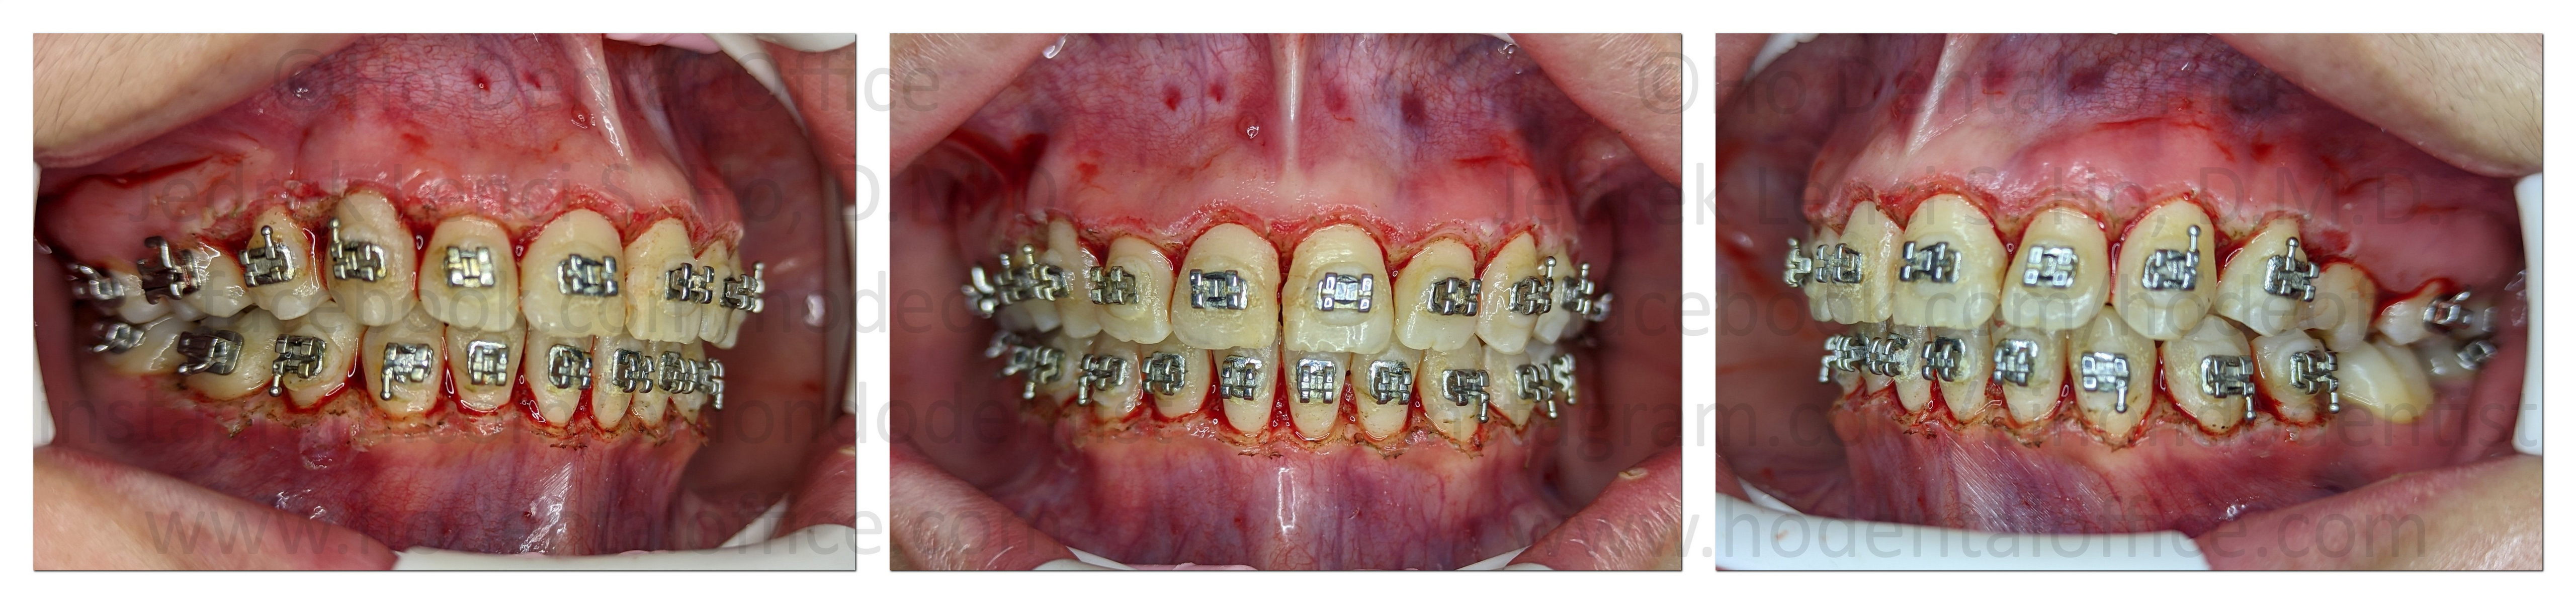

Gingivectomy with gingivoplasty was performed on the patient, under local anesthesia using an electrosurgical unit ("cautery"), on Nov 14, 2022.

As can be seen on the picture above, a lot of gum tissue was cut out. Note the larger tooth appearance on the area of the lower incisors. The borders of the gum surrounding the crowns are also contoured such that they are slightly "beveled."

Patient was dismissed after procedure. Bleeding was very minimal afterwards. Patient was prescribed with pain medication, bleeding control drug, and mouthwash.